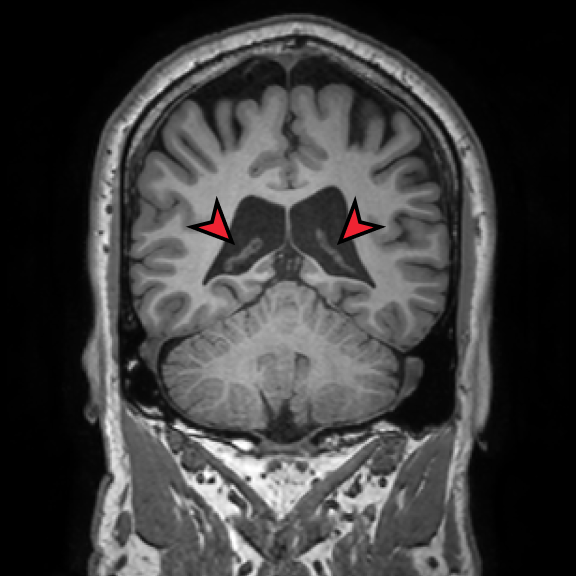

Retrospective brain volumetric analysis in a female patient diagnosed with Alzheimer’s disease at age 77 showed progressive brain atrophy over a 5-year period. The scans demonstrate both hippocampal volume loss and a clear left–right asymmetry.

Retrospective brain volumetric analysis in a female patient diagnosed with Alzheimer’s disease at age 77 showed progressive brain atrophy over a 5-year period. The scans demonstrate temporal cortical atrophy with marked ex-vacuo enlargement of the lateral ventricles.

PATIENT

Female patient diagnosed with Alzheimer's Disease at Age 77

Analysis period

5 years

regions of interest

Hippocampi

Inferior lateral ventricles

Age 72

Age 76

Age 77